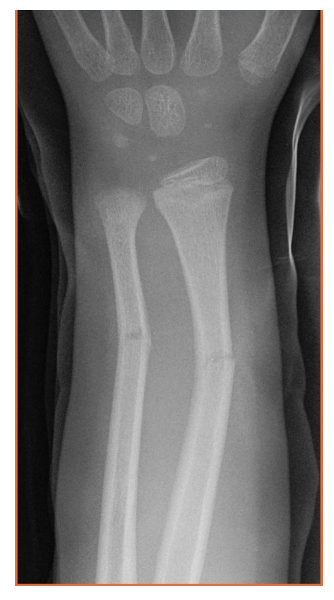

what do you call a fx with incomplete extension through the periosteum? how does this fracture present?

A

greenstick fracture

presents MC in children d/t soft bone. causes fracture on tension side and buckling of the bone on the other side of the shaft of a long bone.